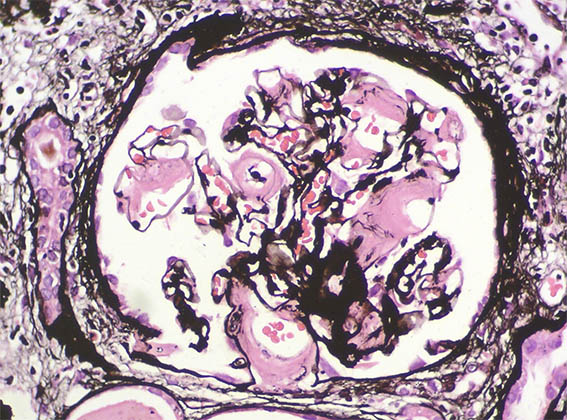

Figura 9. Plata-metenamina, X400.

Figura 10. Plata-metenamina, X400.